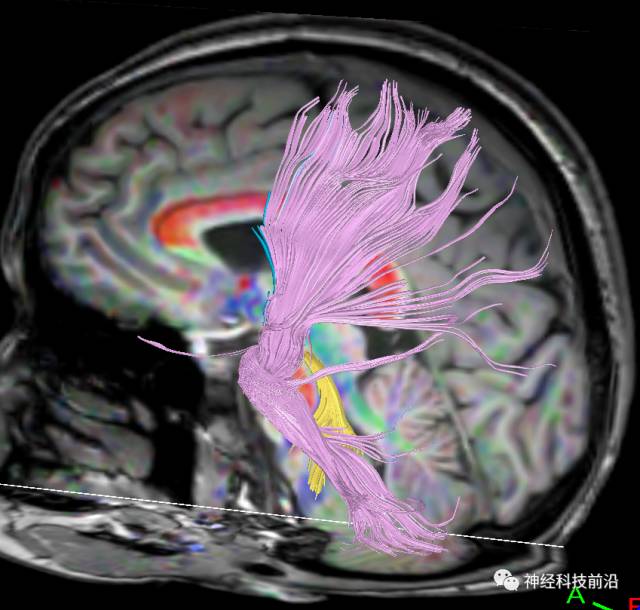

下面为皮质脊髓束的走形及位置

下面为皮质脑桥束的走形方位

皮质脑桥束与脑干高信号(黄色)纤维束

皮质脊髓束与皮质脑桥束的关系毗邻